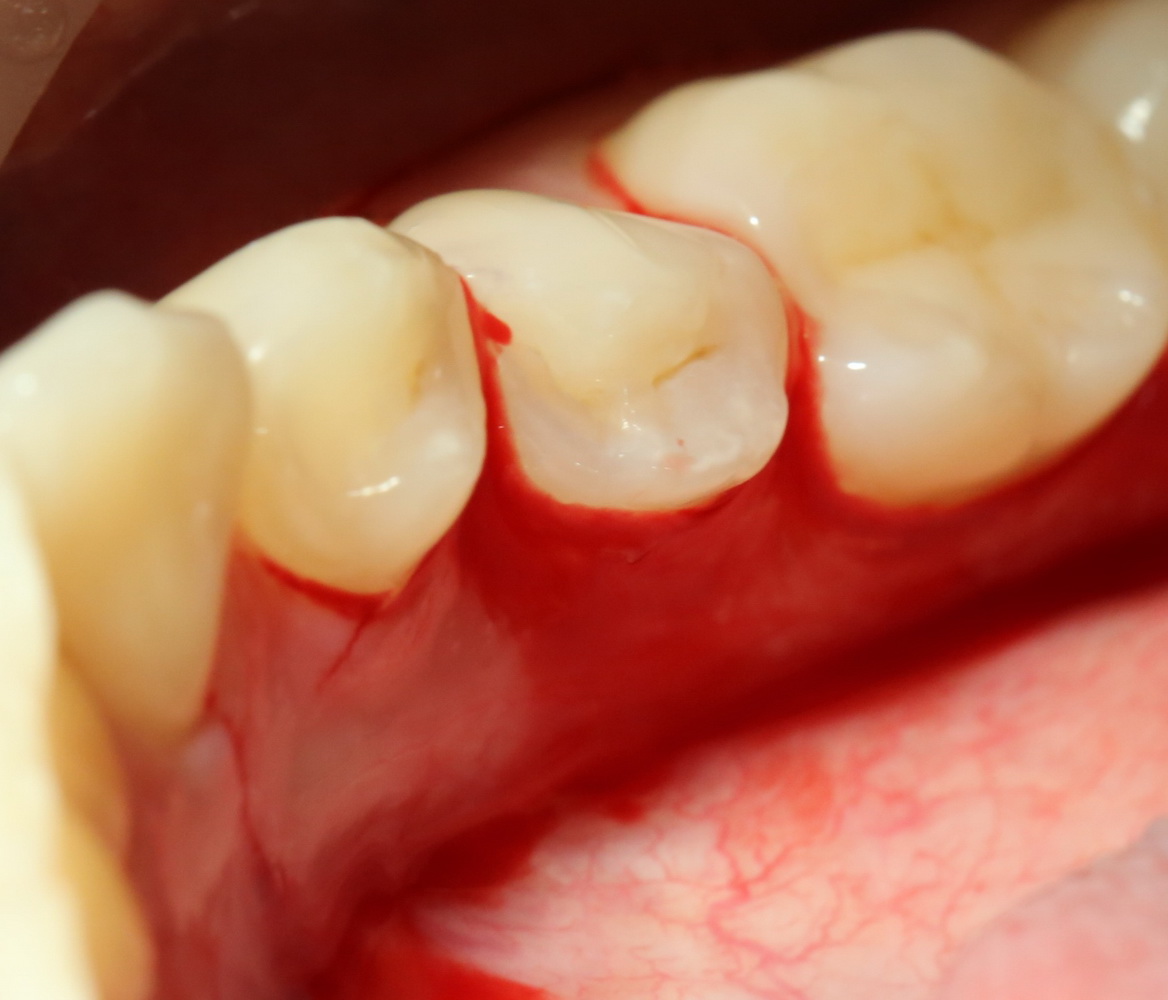

Всё начинается с анестезии и разреза:

Его приблизительная схема показана на картинке справа. Разрез спланирован таким образом, чтобы потом вывести узелки швов на внешнюю сторону — так они будут меньше беспокоить пациента в послеоперационном периоде. К тому же, обзор раны будет лучше.

Для разреза я пользуюсь специальным обоюдоострым микроскальпелем, кстати.

Следует учесть, что с язычной стороны слизистая оболочка более нежная и тонкая. Скелетировать альвеолярный отросток нужно с большой осторожностью: